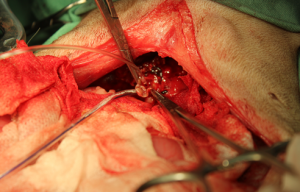

破裂した胆のうを確認しました。

摘出した胆のう内容物です、ゼリーのようにドロドロしています。